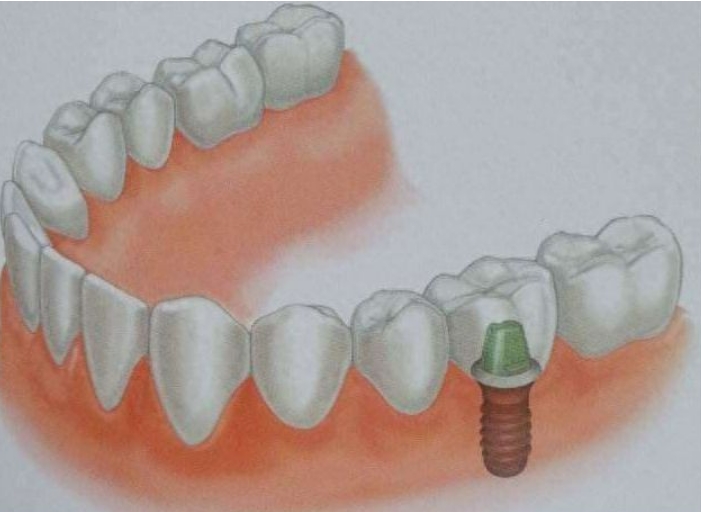

种植牙术后不适感一般会持续多久,这个问题并没有一个确切的答案,因为它受多种因素的影响,包括患者的个人体质、手术的具体情况、术后的护理以及是否存在病理性原因等。

总结,种植牙术后不适感一般会持续一段时间,但具体时间因人而异。在大多数情况下,术后不适感会在3到6个月内逐渐减轻或消失。然而,这并不意味着患者可以忽视术后护理和复诊的重要性。正确的术后护理和及时的复诊可以帮助患者更快地恢复健康,并减少并发症的发生。